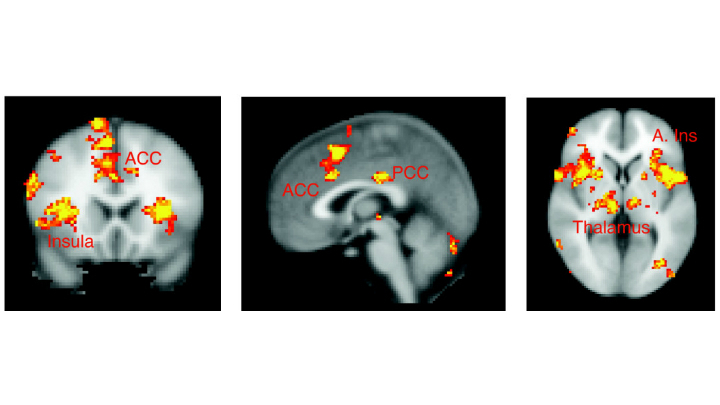

Люди, склонные к гневу имеют проблемы с мозгом . Исследование: Склонность к гневу указывает на проблемы с мозгом Люди, склонные к гневу, часто неверно интерпретируют намерения других людей . Они также плохо воспринимают информацию, поступающую из социального . . .